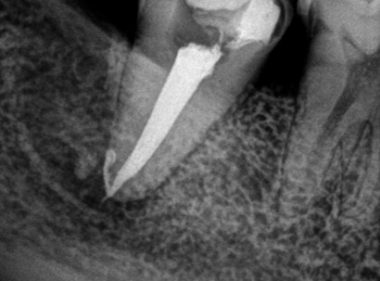

Patient Name:Rakesh Sinha

Tooth Involved :46

Diagnosis :Distocclusal Caries Involving Enamel And Dentin

Treatment :Indirect Restoration With Cuspal Coverage Of Distocclusal Cusp